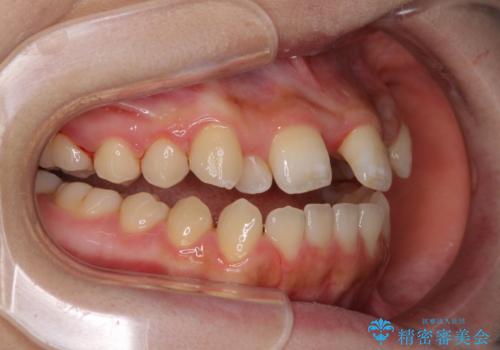

上顎骨を拡大したことで、下顎の歯列を上顎が受け入れられるようになりましたが、インビザラインでは咬み合わせを改善させることができなかったため、ワイヤー矯正にて仕上げることとしました。

ワイヤーを使用したものの、上下前歯のオープンバイトがなかなか改善されませんでしたが、患者希望により治療終了となりました。